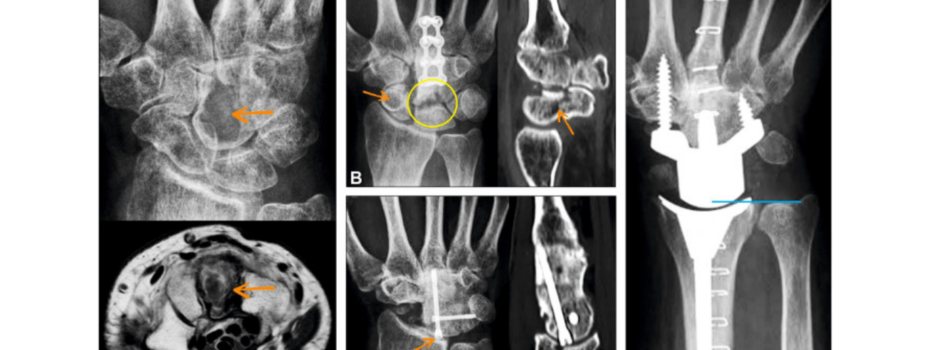

Rysunek 1 Całkowita artroplastyka nadgarstka (TWA) stała się coraz bardziej opłacalną alternatywą dla całkowitej fuzji nadgarstka u pacjentów z ciężkimi chorobami nadgarstka. Jednak długoterminowa skuteczność TWA, szczególnie dotycząca roli śrub blokujących, była przedmiotem trwającej debaty. Niedawne studium przypadku dr Ingo Schmidta z prywatnej praktyki Othopeedic w Niemczech, opublikowane w Journal of Hand Surgery Global Online, […]